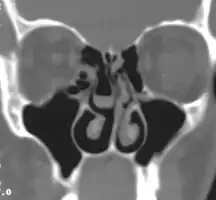

Concha bullosa

Concha bullosa on both sides (marked with asterisks), coronal orientated image from CT

A concha bullosa is a pneumatized (air-filled) cavity within a nasal concha, also known as a turbinate.[1]

Bullosa refers to the air-filled cavity within the turbinate.[1] It is a normal anatomic variant seen in up to half the population. Occasionally, a large concha bullosa may cause it to bulge sufficiently to obstruct the opening of an adjacent sinus, possibly leading to recurrent sinusitis[1] and various head pains related to areas innervated by the trigeminal nerve.[2] In such a case the turbinate can be reduced in size by endoscopic nasal surgery (turbinectomy). The presence of a concha bullosa is often associated with deviation of the nasal septum toward the opposite side of the nasal cavity.[3]